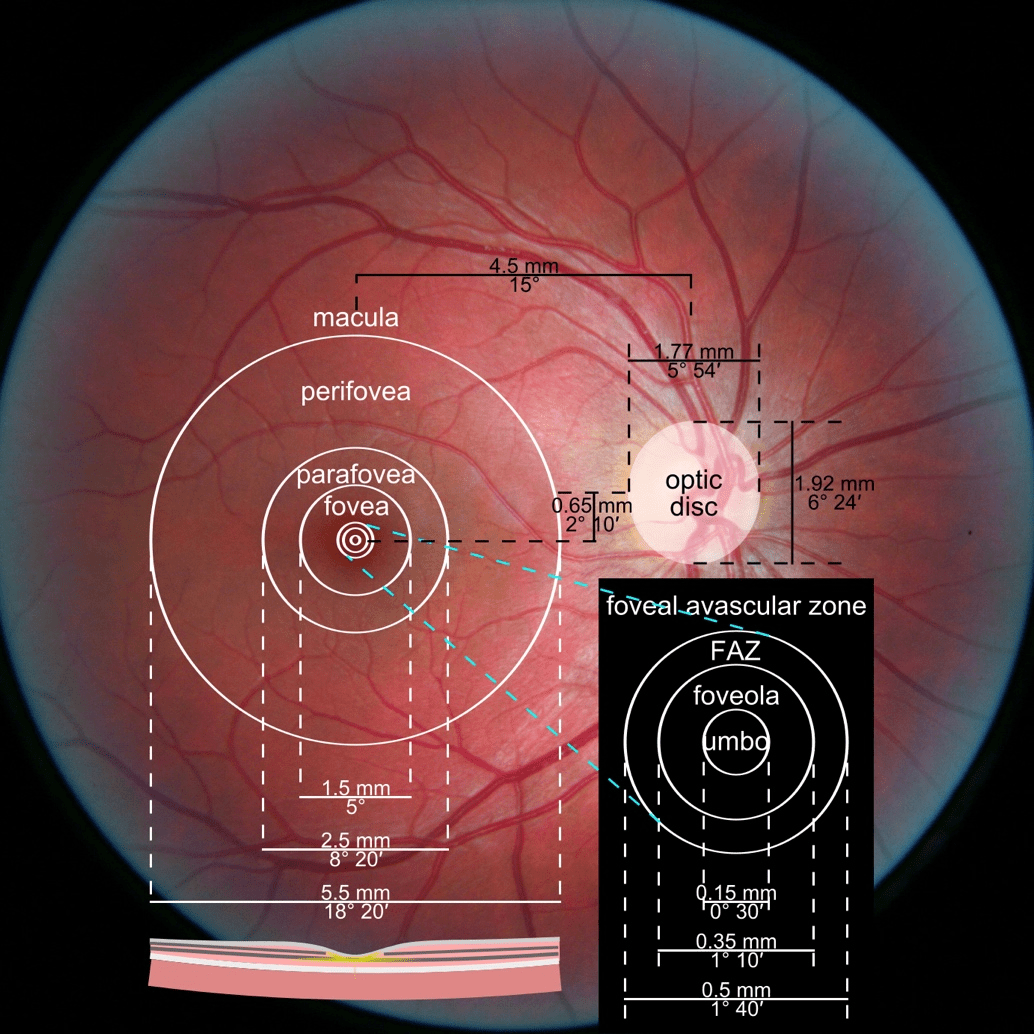

While retinal reports vary among OCT models, they typically include:- a foveally centered B-scan,

- a quantitative thickness map,

- and a semi-quantitative thickness map.

The B-scan offers a visual snapshot of foveal architecture and confirms proper scan centering. The quantitative thickness map employs the ETDRS sector map to measure retinal thickness within a 6mm circle around the fovea, with specific measurements for the foveal sector (1mm), inner macular ring (3mm), and outer macular ring (6mm).

Progression analytics enable comparison of serial macular scans, which is invaluable for managing vitreomacular interface disorders and macular edema. The semi-quantitative thickness map provides a broader overview of retinal thickness throughout the scan.

In current clinical practice, macular damage assessment typically involves measuring the distance between the ILM and RPE layers, summarized in a post-scan report.